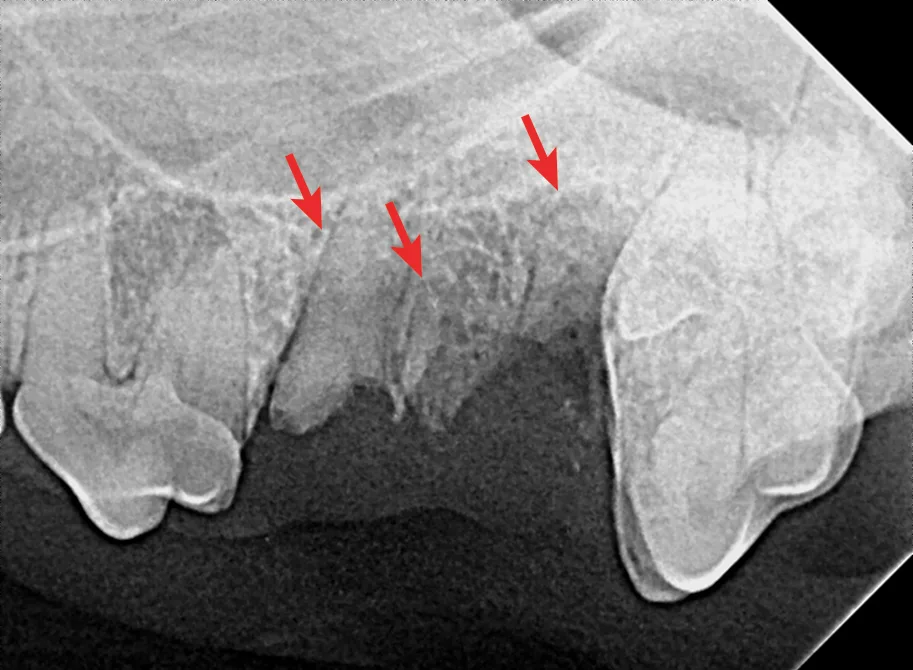

FIGURE 2

Right maxillary premolar tooth root in the nasal cavity (A; circle) and root fragment after removal from the nasal cavity (B)

Root removal from the nasal cavity can be especially difficult because of the large size of the nasal cavity and the potential for tooth root migration. Large mucoperiosteal flaps, bone windows, and suction can aid in the removal process. Avoiding the mandibular neurovascular structures when removing roots from the mandibular canal can be challenging but is crucial, as hemorrhage can occur if structures are punctured.